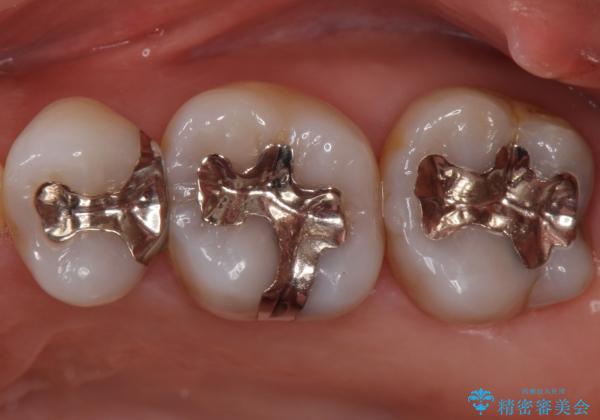

- 左上567 セラミックインレー:77,000円×3本費用は治療当時の料金となります

大きな虫歯さえなければ、銀歯のやり替えは詰め物の周りの歯を保存しつつ修復することができます。